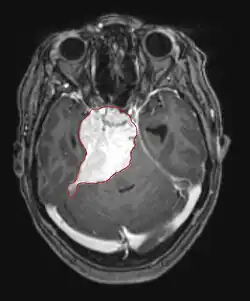

Imaging

• CT

• Well-defined extra-axial mass that displaces normal brain. Smooth in contour, sometimes calcified

• About 60% hyperdense with normal brain without contrast

• About 70% brightly and homogenously enhance with contrast (less frequent in malignant or cystic meningiomas)

• MRI

• Preferred imaging because it can show dural origin

• Dural tail sign seen in about two-thirds: characteristic marginal thickening that tapers peripherally along the dura

• Isointense on T1, hyperintense (usually homogeneously) on T2, strong enhancement with IV contrast